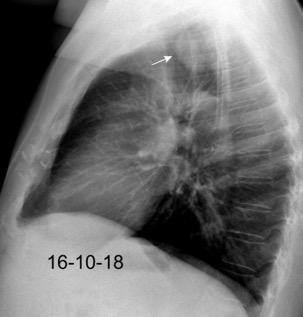

Neumonía a neumococos base izda. con derrame que aumenta.

Broncograma en lateral y en US.